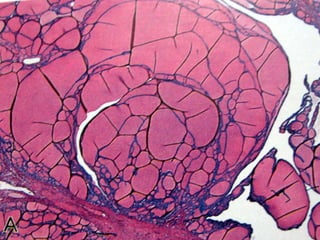

Câncer de Tireóide

Carcinoma Folicular



15 – 20 % dos casos

É mais freqüente em regiões com carência de Iodo

Maior incidência na quinta década

Se apresentam como um nódulo

15 – 20 % o diagnóstico é feito a partir do encontro de uma

metástase

Raramente dão metástase cervical

Podem ser minimamente ou amplamente invasivos

Têm disseminação hematogênica para pulmões, ossos,

fígado e cérebro

Câncer de Tireóide CarcinomaFolicular         15 – 20 % dos casos É mais freqüente em regiões com carência de Iodo Maior incidência na quinta década Se apresentam como um nódulo 15 – 20 % o diagnóstico é feito a partir do encontro de uma metástase Raramente dão metástase cervical Podem ser minimamente ou amplamente invasivos Têm disseminação hematogênica para pulmões, ossos, fígado e cérebro